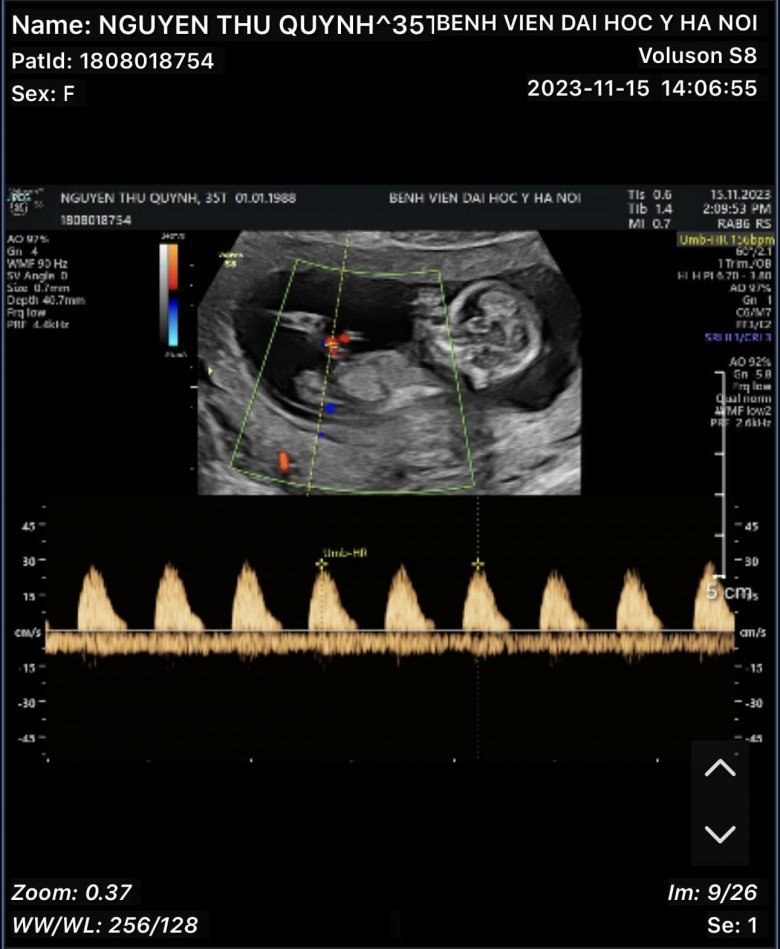

Kèm theo đó, nữ diễn viên còn đăng tải bức hình chụp em bé trên phiếu siêu âm. Qua hình ảnh siêu âm, mọi người đoán em bé của Thu Quỳnh được khoảng 3 tháng.

Qua hình ảnh siêu âm, mọi người đoán em bé được khoảng 3 tháng.